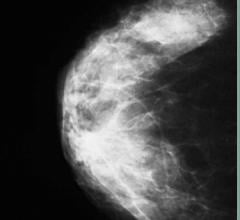

Despite decades of progress in breast imaging, one challenge continues to test even the most skilled radiologists ...

The accurate measurement of mammographic density offers the potential to improve breast cancer risk prediction and to tailor screening protocols according to risk, according to a study published in Breast Cancer Research (16:439 doi:10.1186/s13058-014-0439-1). The article, “Digital mammographic density and breast cancer risk: a case-control study of six alternative density assessment methods,” demonstrates a strong connection between breast density and breast cancer risk.